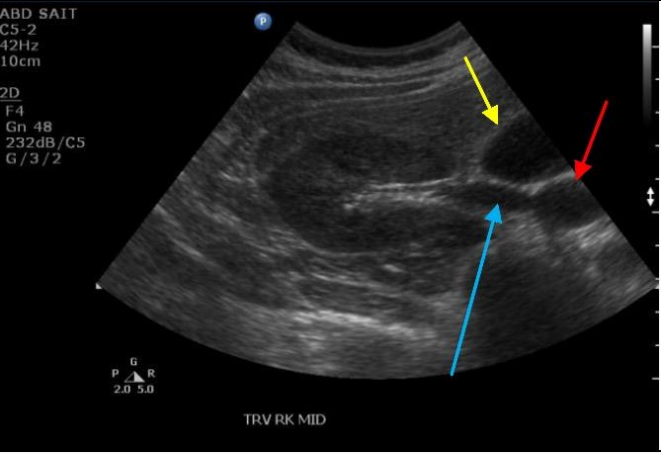

7

Q

Label the Red and blue arrows

A

Red: Right quadratus laborum

Blue: Right kidney pyramid of the medulla